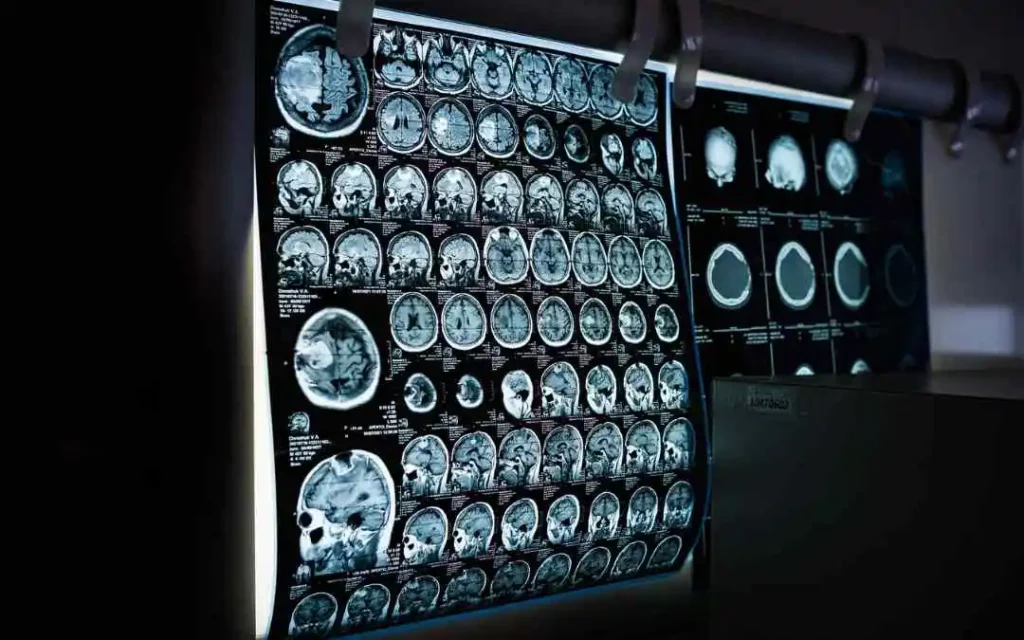

Computed tomography (CT) scans

CT scans are commonly used to diagnose cancer, heart disease, and other conditions. These use a special type of X-ray machine that rotates around the body to produce multiple images from different angles. A computer then combines these images to create a detailed 3D image of the body.

An X-ray scan measures the density of the structures in the body that the beam passes through. Dense structures, such as bones, appear white on the X-ray, while less dense structures, such as organs, appear gray. This contrast in density allows the radiologist to identify abnormalities or damage to the structures in the body.